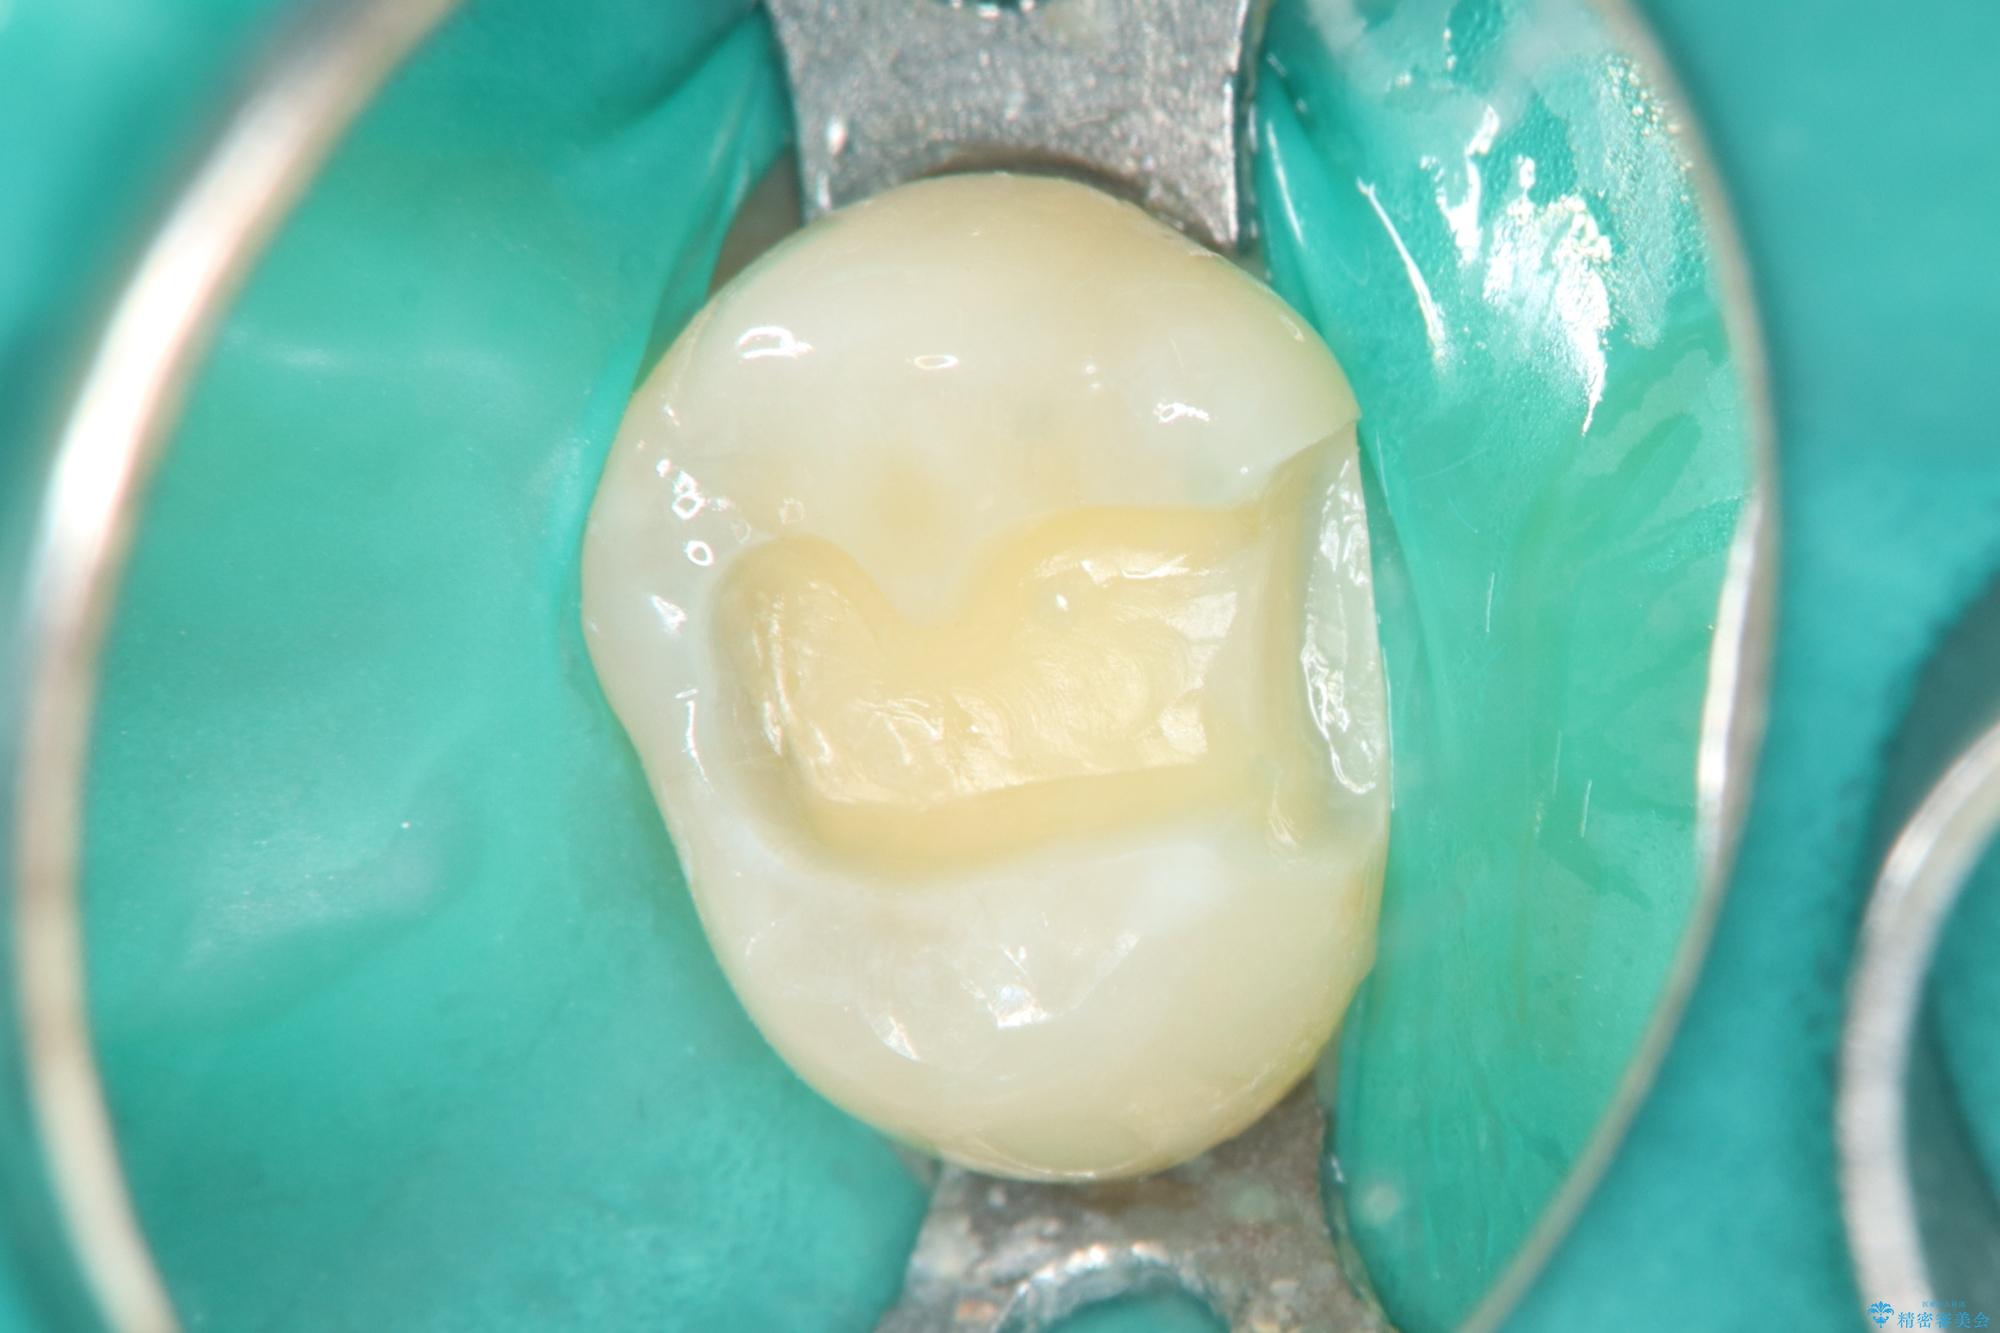

今回の治療では、虫歯の大きさや深さに応じて、異なるセラミック修復法を適用しました。

比較的軽度な虫歯には、セラミックインレー(詰め物)で対応し、健全な歯質を最大限に残しました。

進行した虫歯や歯の強度が低下している歯には、セラミッククラウン(被せ物)を選択し、歯全体を保護することで破折を防ぎました。

短期間での治療を可能にしつつ、天然歯と見分けがつかない審美性と、長期的に安定する機能性を兼ね備えたセラミック修復を実現しました。